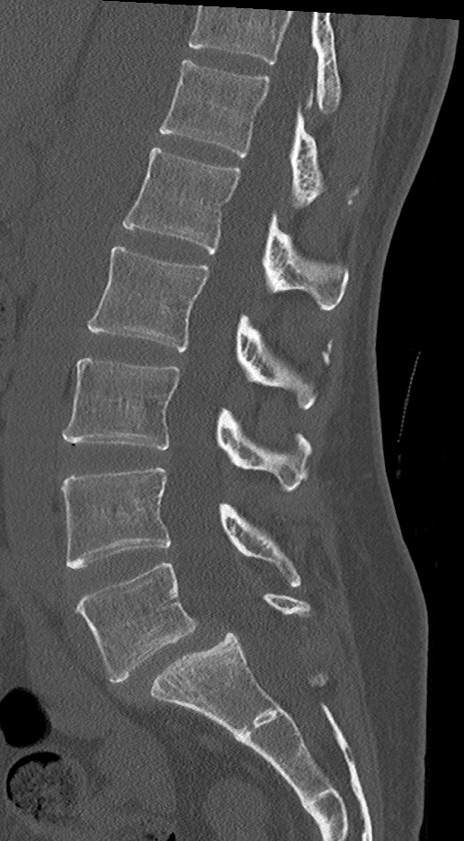

【整形】TIPS症例4 腰椎CT(矢状断像)

腰椎CT